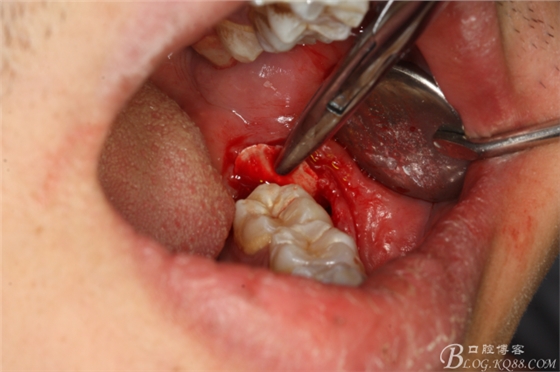

圖12.牙冠取出后,為牙根的脫位騰出空間

圖13,牙槽窩周圍牙齦幾乎無(wú)損

圖14.挺子放頰側(cè)骨板,以頰側(cè)骨板做支點(diǎn)